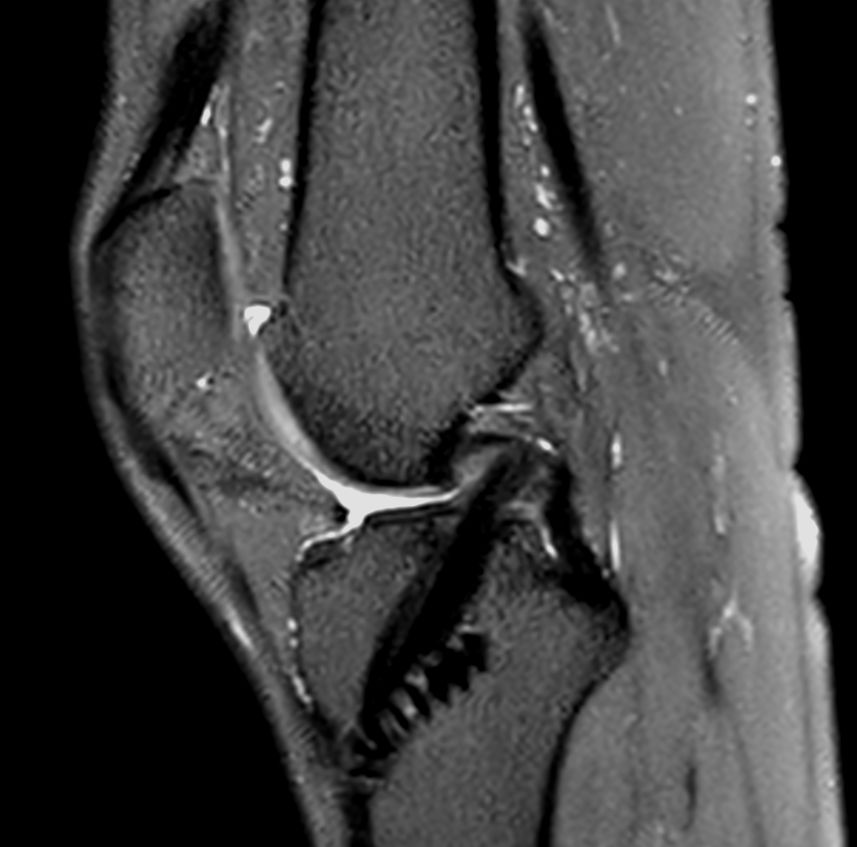

Knee ACL repair

Axial T2w TSE

Coronal T1w TSECompressed SENSE

Sagittal PDw SPAIRCompressed SENSE

Coronal PDw SPAIRCompressed SENSE

Sagittal 3D PDw SPAIRCompressed SENSE

Coronal 3D PDw SPAIR (reformat)Compressed SENSE